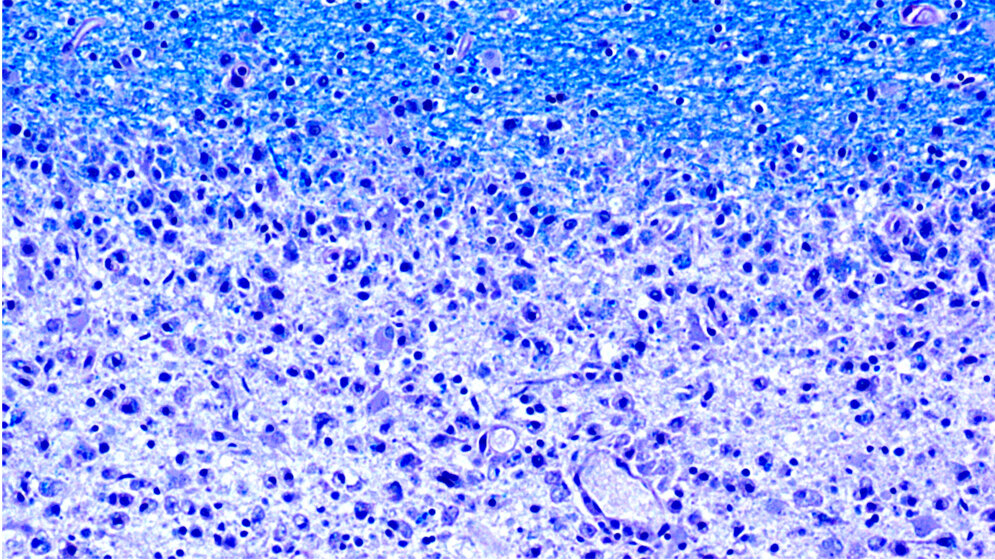

Die Multiple Sklerose (MS) ist eine Autoimmunerkrankung, bei der sich das körpereigene Abwehrsystem gegen die Hüllen von Nervenzellen richtet und sie zusehends zersetzt. Weil diese Hüllen aus so genanntem Myelin – einer biologischen Membran aus Fetten und Eiweißen – bestehen, konzentrierte sich die Wissenschaft auf ihrer Suche nach den Zielantigenen der Krankheit bisher auf Myelinkomponenten. Doch nun legen neue Resultate der Forschungsgruppe um Mireia Sospedra und Roland Martin vom Klinischen Forschungsschwerpunkt Multiple Sklerose der Universität Zürich nahe, dass es sich lohnt, den beschränkten Blickwinkel zu erweitern, um ein besseres Verständnis des Krankheitsgeschehens zu gewinnen.